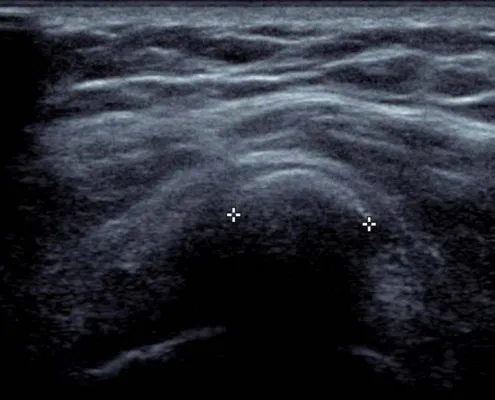

Il consiste en une Ponction Lavage Aspiration sous contrôle échographique.

L’aiguille est placée parallèlement au grand axe de la calcification.

Une forte pression est appliquée sur le piston pour fragmenter la calcification (la première seringue utilisée peut être remplie de xylocaïne pour limiter les douleurs).

Recueil du mélange sérum + boue calcique

Quand le piston est relâché, le liquide injecté, chargé de boue calcique, remonte dans la seringue. Quand le contenu de la seringue est trop chargé en calcium, une nouvelle seringue est utilisée jusqu’à ce que le liquide refoulé soit clair.

Le contrôle échographique va permettre d’amener la pointe de l’aiguille dans toutes les régions calcifiées sans changer de point d’entrée cutanée et sans effet délétère sur le tendon.